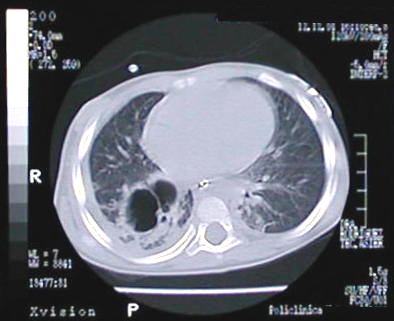

Corte Tomográfico " 5 "

Corte a nivel de base del tórax:

Parenquima pulmonar de aspecto normal excepto el segmento posterobasal del lóbulo inferior derecho donde observamos cavidad bilobulada sacular de paredes engrosadas rodeado de parenquima pulmonar de aspecto neumónico.